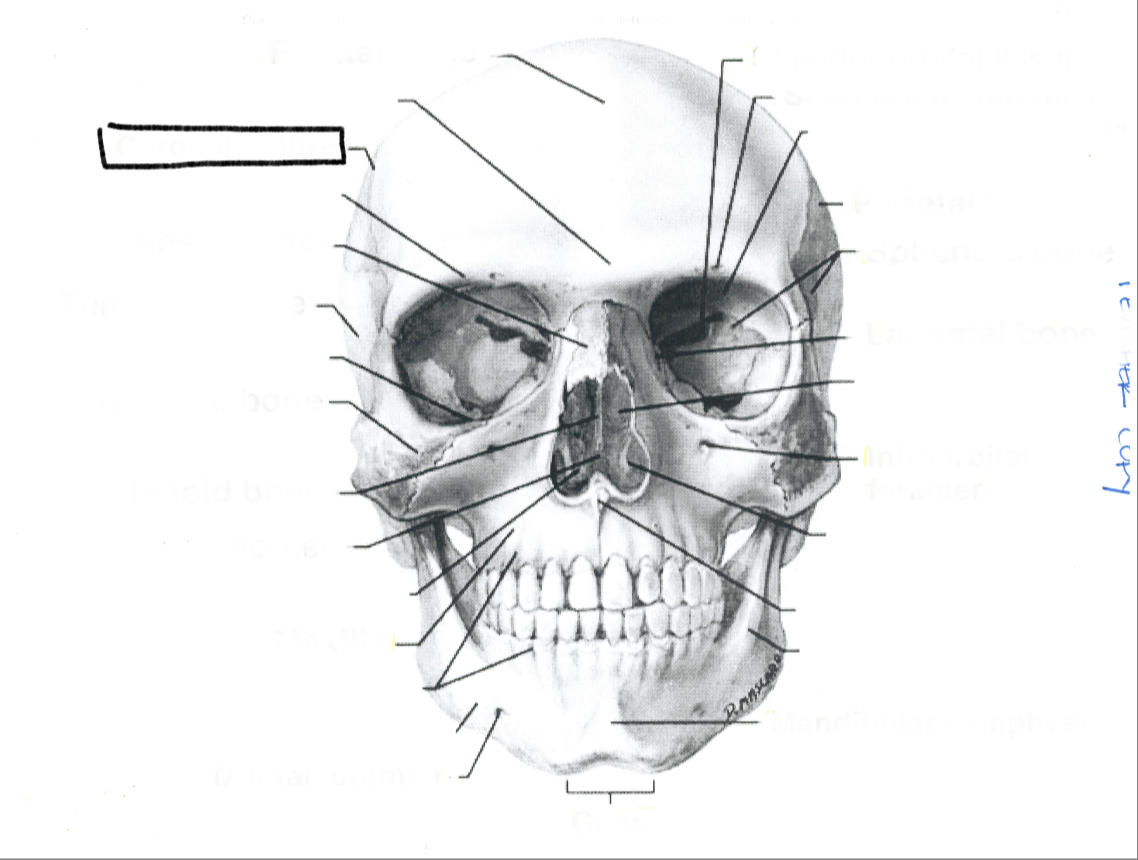

What is this?

Lacrimal bone

What is this?

Sphenoid bone

What is this?

Parietal bone

What is this?

Infraorbital foremen

What is this?

Supraorbital foramen

What is this?

Superior orbital fissure

What is this?

Mandibular symphysis

What is this?

Genu

What is this?

Mental foramen

What is this?

Maxilla

What is this?

Ethmoid bone

What is this?

Zygomatic bone

What is this?

Temporal bone

What is this?

Nasal bone